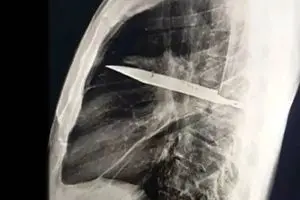

کشف عجیب در قفسه سینه؛ چاقویی که ۸ سال در بدن مردی جا خ...

در یکی از نادرترین موارد پزشکی ثبت‌شده، مردی ۴۴ ساله اهل تانزانیا با ترشح چرک از...